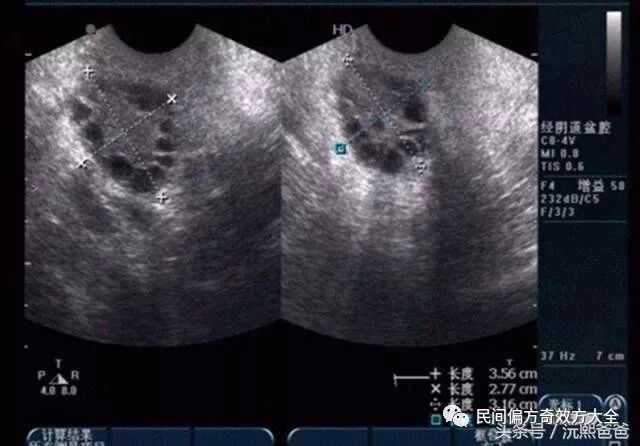

第一个就是:彩超检查。其实,更好的是内(阴)超检查。因为更加清晰地可以看出两侧的卵巢是否呈现多囊的状态。因为多囊卵巢用大白话来说,就是卵泡长不大或者是不排卵,在卵巢上集聚在一起,使得卵巢越来越大,彩超检查的时候,卵巢有超过十个以上的小卵泡就可以确证为多囊。

2. 彩超检查直接确诊多囊卵巢。